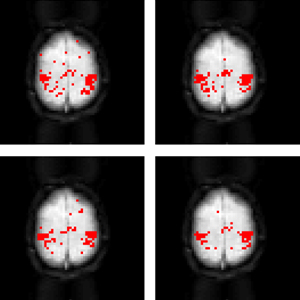

Motor cortex network recovery with agglomerative

clustering (top right), temporal mapping of proximity

(top left), Louvain method (bottom right) and spectral

clustering (bottom left).

We are currently performing validation studies with our MCA framework for purposes of recovering the primary motor cortex network associated with hand movement. Our end goal is to apply our framework for quantifying differences in cognitive functional connectivity between healthy subjects and patients suffering from HIV-induced cognitive impairment.